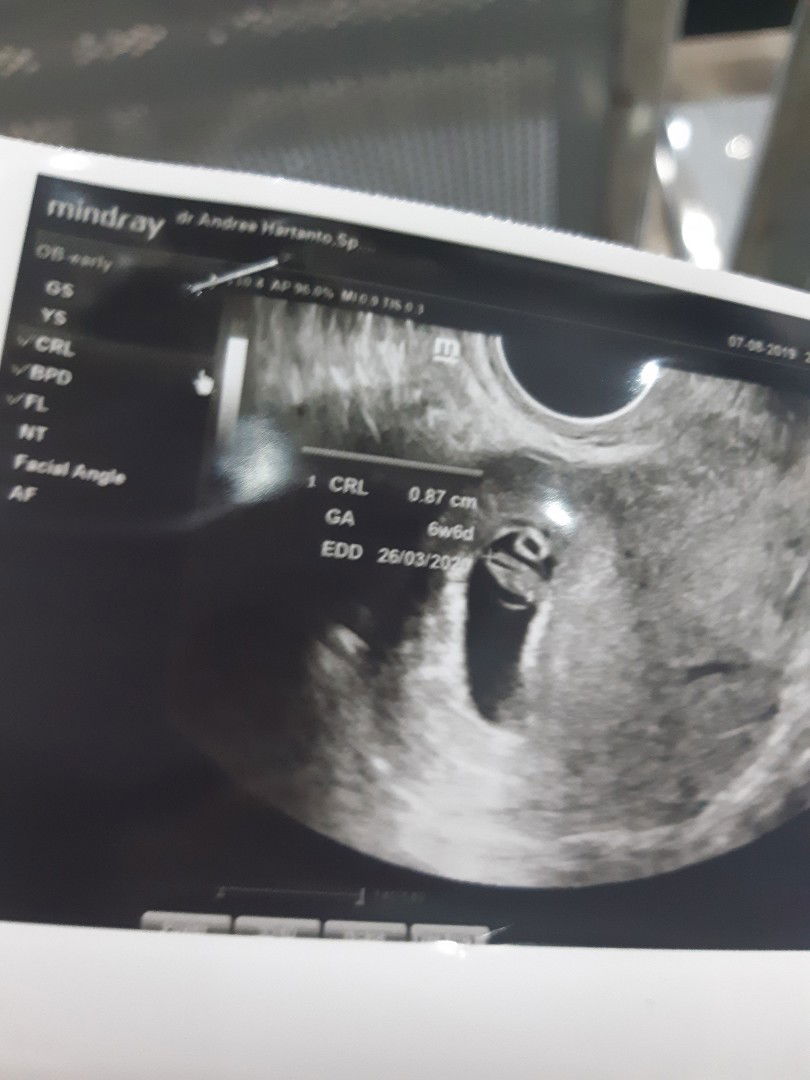

Alhamdulilah ya bun semalam aku usg usia kandungan 6w6d aka 7w.. aku usg transvaginal dan udh kedengeran detak jantungnya...seneng banget... tp kt dokter aku dan suami dilarang berhubungan dulu, trus di kasi penguat kandungan utrogestan. Bunda ada yg diresepin itu juga ga??? Sbnrnya penguat kandungan butuh banget ga sih??? Udh aku tebus sih resepnya selain utrogestan ada bbrp vitamin juga obat antimual, soalny lg lemes2nya ini. Tp mahal bet ya nebus resep sampe 1,2jt..utrogestannya tuh harganya mahal banget. Kl misalny disuruh kontrol lg trus dikasi utrogestan lg tp aku ga ambil kira2 ngefek ga ya ke perkembangan si janin atau kandungan???